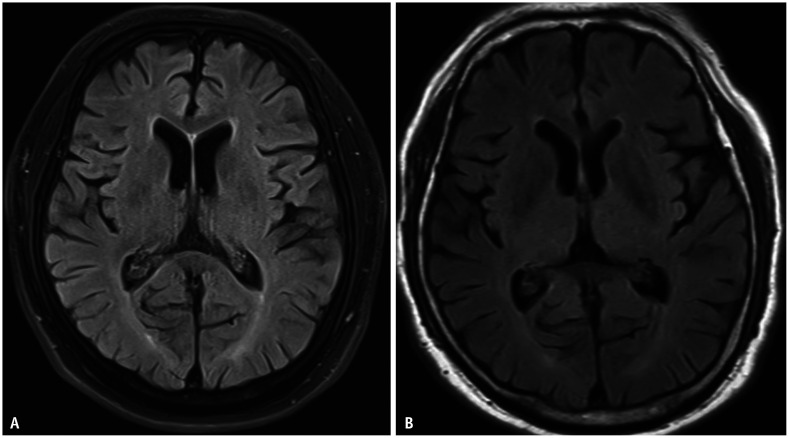

Clinical trials for chimeric antigen receptor (CAR) T-cell therapy are in the early stages but are expected to progress alongside new treatment approaches. This suggests that imaging will play an important role in monitoring disease progression, treatment response, and treatment-related side effects. There are, however, challenges that remain unresolved, regarding imaging in CAR T-cell therapy. We herein discuss the role of imaging, focusing on how tumor response evaluation varies according to cancer type and target antigens in CAR T-cell therapy. CAR T-cell therapy often produces rapid and significant responses, and imaging is vital for identifying side effects such as cytokine release syndrome and neurotoxicity. Radiologists should be aware of drug mechanisms, response assessments, and associated toxicities to effectively support these therapies. Additionally, this article highlights the importance of the Lugano criteria, which is essential for standardized assessment of treatment response, particularly in lymphoma therapies, and also explores other factors influencing imaging-based evaluation, including emerging methodologies and their potential to improve the accuracy and consistency of response assessments.